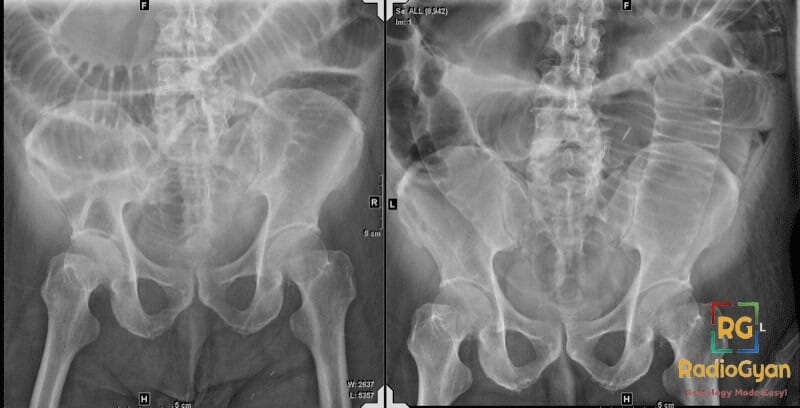

Riglerโs sign is caused by pneumoperitoneum, which is the presence of free gas in the peritoneal cavity. This free gas outlines both the inner (luminal) and outer (serosal) surfaces of the bowel wall, making both sides visible on plain abdominal X-rays.

Normally, only the luminal side of gas-filled bowel walls is visible on X-rays because the surrounding soft tissues obscure the outer wall. When free gas accumulates in the peritoneal cavity (pneumoperitoneum), it collects around bowel loops. This gas surrounds the bowel walls externally, providing contrast against the soft tissues. Consequently, the bowel wall is outlined on both sides, producing a โdouble wallโ or Riglerโs sign.